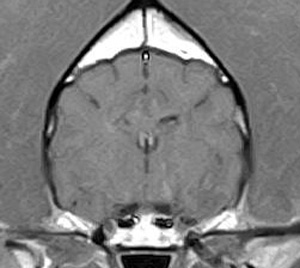

けいれん発作が出るワンちゃんが来院されました。MRI検査では脳に構造上の異常を認めず、特発性てんかんとの診断でお薬での治療となりました。発作は現在のところ、お薬で良好にコントロールされています。